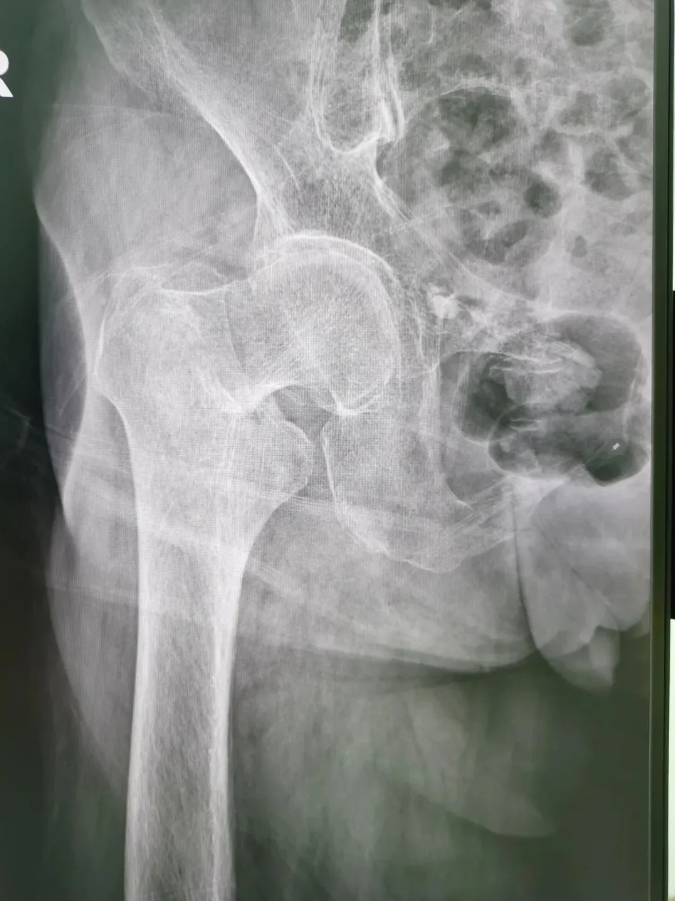

今年91歲的陳婆婆,9月份時在家不慎摔倒,右臀部著地,當下感到髖部劇烈疼痛并活動受限。為求進一步治療,到順德和平外科醫院骨三區就診,該區主任楊升平主任為其診療,被診斷為“右股骨頸骨折”,需進行右股骨頸骨折經皮閉合復位空心螺釘內固定手術。

1606114819447309.png

術前X光

陳婆婆91歲的高齡,有高血壓和冠心病病史,通過傳統開刀手術治療風險較大。經骨三區專業醫療團隊討論,決定讓天璣?骨科機器人上場,輔助完成微創手術。